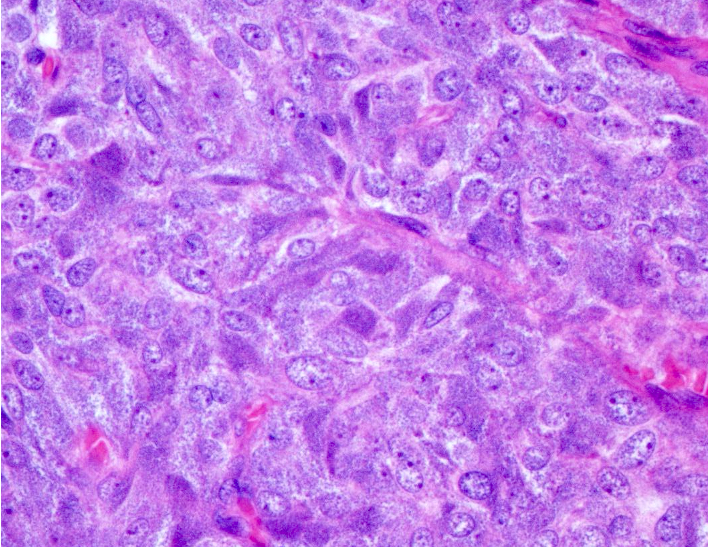

Microscopic (histologic) description

- Typical morphology: epithelioid cells with abundant, eosinophilic / amphophilic, granular cytoplasm and round / ovoid, vesicular / salt and pepper nuclei, arranged in a nested / zellballen pattern and separated by fibrovascular septae with sustentacular cells (Am J Surg Pathol 2004;28:94, World J Clin Cases 2014;2:591, Endocr Pathol 2022;33:90)

- May have focal pleomorphism, nuclear hyperchromasia, low mitotic activity or clear cytoplasm

Microscopic (histologic) images

Contributed by Theodorus H. van der Kwast, M.D., Ph.D., Michelle R. Downes, M.D., Debra L. Zynger, M.D. and David Cohen, M.B.B.Ch., M.D.

- Microscopic description: This specimen shows an unencapsulated, monomorphous population of round tumor cells in a nested / zellballen pattern with delicate vascular septa and intervening extravasated red blood cells. It predominantly involves the lamina propria of the bladder but in 1 tissue piece clearly involves muscularis propria. The tumor cells have abundant amphophilic cytoplasm and vesicular chromatin with occasional small nucleoli. There is no necrosis, diffuse growth pattern or vascular space invasion identified. The mitotic count is (maximally) 1/10 high power fields. Immunohistochemistry shows the tumor cells to be positive for GATA3 with strong and diffuse expression of synaptophysin and chromogranin, as well as retention of SDHB staining. The tumor cells are negative for AE1 / AE3, HMWK and p63. The Ki67 proliferation index is < 1%. S100 shows faint nuclear and cytoplasmic staining with occasional sustentacular cells identified.

- Microscopic description: Sections show unremarkable surface urothelium with a lesion in the deep lamina propria comprised of large eosinophilic cells with hyperchromatic, focally enlarged nuclei with occasional intranuclear inclusions. A fine vascular plexus is identified in some areas. Necrosis and hemorrhage are not identified. Mitotic rate = 1/10 high power fields (field of view [FOV] = 0.55 mm). The lesion extends to the cauterized base of the specimen. Immunostains confirm the lesion expresses synaptophysin, chromogranin and GATA3. SDHB is retained. AE1 / AE3, CD45, p63 and NKX3.1 are negative.